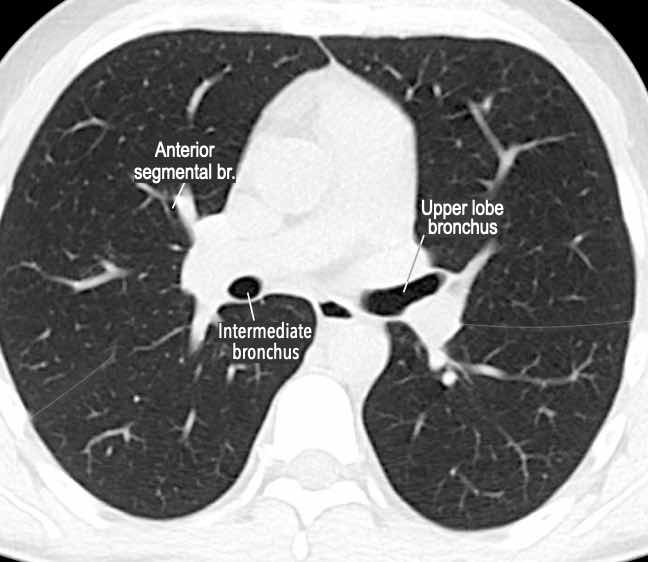

Phế quản trên CT

Cuộn qua các hình ảnh để quan sát khí quản phân chia thành phế quản chính phải và trái, sau đó tiếp tục phân chia thành các phế quản thùy và phế quản phân thùy.